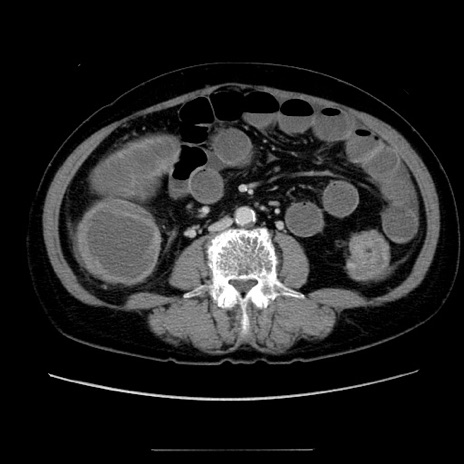

症例5(横断像)

【症例】70歳代女性

【主訴】お腹が張る

【現病歴】1週間くらい前から腹部膨満の自覚あり。昨日夜から増悪したため、本日救急外来受診。

【身体所見】意識清明、BT 36.5℃、BP 165/106mmHg、HR 80bpm、SpO2 98%、腹部:膨満、軟、自発痛・圧痛なし、触診にて不快感あり、腸蠕動音:減弱

【データ】WBC 12600、CRP 1.04